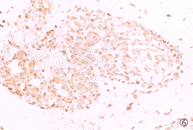

图1 鼻咽未分化癌,可见位于细胞间和细胞内的凋亡小体。HE×200

38例鼻咽癌组织中,bcl-2的阳性表达率为97.4%(37/38)(图3)。在37例阳性病例中,bcl-2阳性瘤细胞百分数的中位数为90%,即90%左右的瘤细胞均过表达bcl-2。38例鼻咽癌组织中bax的阳性表达率为100%(38/38)(图4)。Bax阳性瘤细胞百分数的中位数70%,即70%左右的瘤细胞均过表达bax。在38例鼻咽癌组织bcl-2和bax阳性瘤细胞百分数的散点分布图中,可见绝大多数散点均集中位于高表达区内(图5)。在38例鼻咽癌组织中,37例(97.4%)均有不同数量(5%~100%)的p53阳性瘤细胞(图6)。超过20% p53阳性瘤细胞的鼻咽癌组织有29例。如果以此为p53过表达的标准,则p53的过表达率为76.3%(29/38)。

图3 鼻咽未分化癌,大多数癌细胞呈bcl-2胞浆、胞膜阳性。LSAB×50